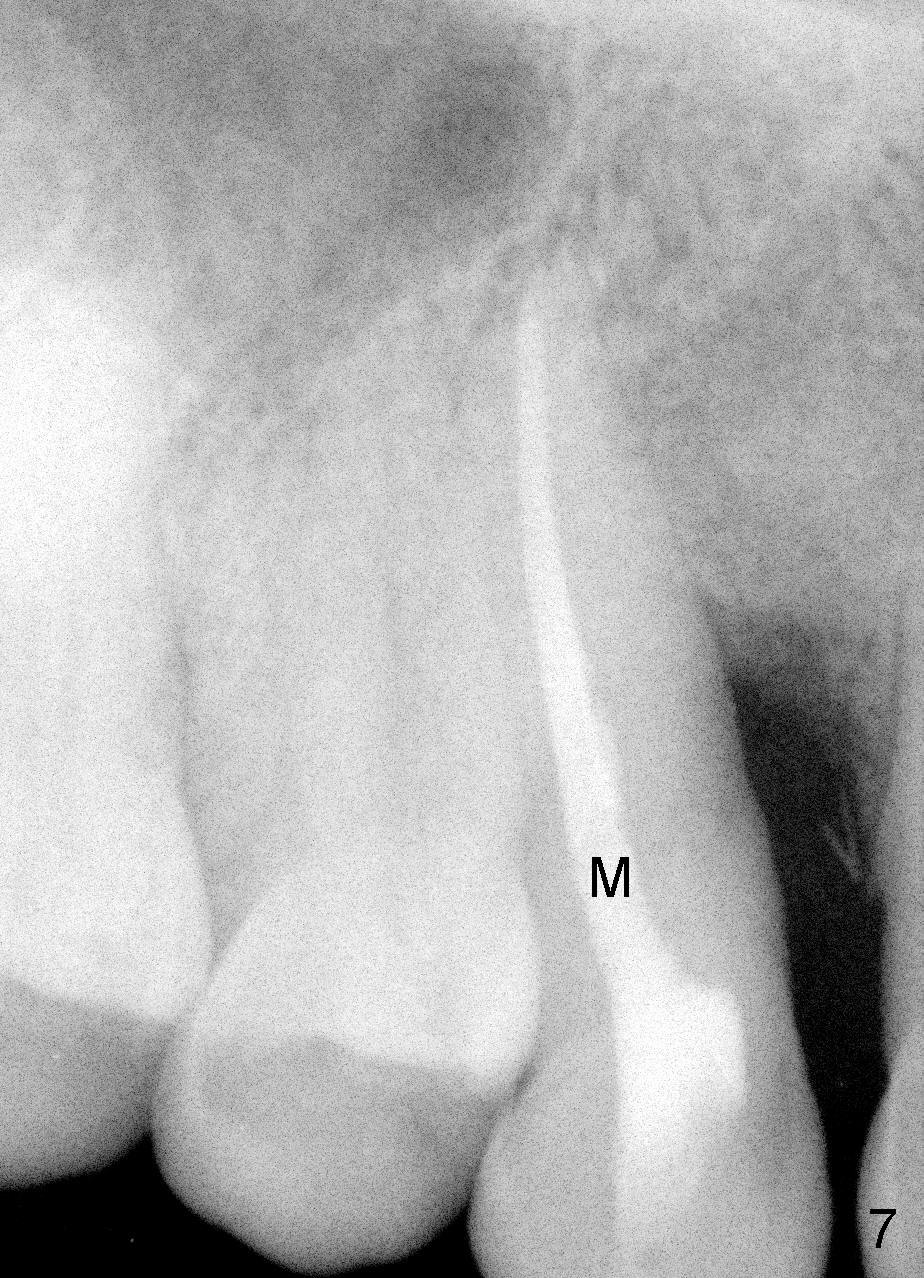

A male patient had trauma to the tooth #6 at the age of 13.  The affected tooth has remained asymptomatic for more than 30 years (Fig.1).   X-ray reveals an oblique root fracture (Fig.2 >) with radiolucency in the mesial alveolus (*, apparently normal trabecular pattern).  Six years later (Feb. 2011), an acute infection develops (Fig.4 *).  It requires incision & draining and antibiotic.  At that time, the trabecular pattern disappears around the fracture line mesially (Fig.3 *).  Four months later cone beam CT shows bone loss between #6 and 7 (Fig.5 *).  Root canal therapy is done as a palliative measure (Fig.6 R; C: Cavit).  Three months later, MTA (mineral trioxide aggregate) is placed in the coronal canal next to the fracture line (Fig.7 M).  It is hoped that MTA can promote nearby bone and cementum to regenerate to seal the fracture line.  Four months after MTA application, there is no sign of bone regeneration (Fig.8).  Bone is lost for approximately 7 mm.